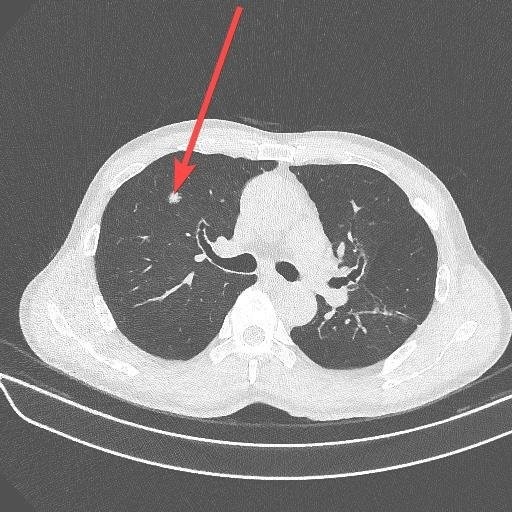

Hình ảnh nốt phổi trước khi được phẫu thuật qua phim chụp CT. Ảnh: Bệnh viện cung cấp

Vì đặc thù công việc, ông Hiếu thường xuyên hút thuốc lá và uống rượu bia. Cách đây 5 năm, do có bệnh tăng huyết áp và đái tháo đường, ông quyết tâm bỏ dần thuốc lá vì tác hại của nó. Tháng 6 năm ngoái, ông đến Bệnh viện Đa khoa Tâm Anh TP HCM khám tổng quát, tình cờ phát hiện một nốt đặc ở phổi trên phim chụp X-quang. Kết quả chụp cắt lớp vi tính (CT) liều thấp cho thấy, khối u gần 7 mm nằm gọn ở thùy trên phổi.

Lần tái khám sau, kích thước nốt phổi tăng lên hơn 9 mm. Sau hội chẩn, bác sĩ quyết định phẫu thuật nội soi lồng ngực nhằm cắt trọn khối u. Trong ekip trực tiếp phẫu thuật cho ông Hiếu, bác sĩ Trần Quốc Hoài, khoa Phẫu thuật Tim mạch - Lồng ngực, cho biết cuộc phẫu thuật kéo dài gần 3 giờ đã loại bỏ u và lấy toàn bộ hạch trung thất để gửi giải phẫu bệnh. Bệnh nhân hồi phục tốt, xuất viện 2 ngày sau mổ và được bác sĩ hướng dẫn chế độ theo dõi tập luyện, trị liệu hô hấp.